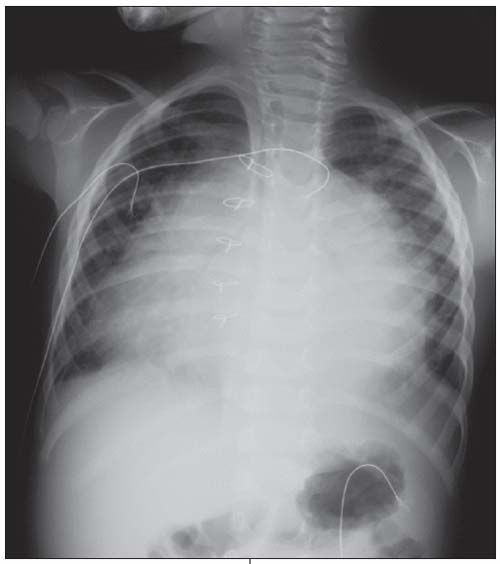

A 3-year-old boy with chest pain and trouble breathing was brought to the ED. His most prominent symptom was a cough, and the chest pain appeared to worsen with coughing. He had undergone open atrial septal defect (ASD) repair about 3 weeks earlier. Cardiovascular examination revealed normal rhythm, with distant heart sounds. The chest radiograph shows massive enlargement of the heart in a globular shape, indicative of a large pericardial effusion.

The boy had postpericardiotomy syndrome, the development of pericarditis or symptomatic pericardial effusion days or weeks after a cardiac operation. ASD repair is a common cause.

Precordial or pleural chest pain is a frequent presenting symptom. Young children may initially have anorexia and vomiting, presumably from bowel ischemia. Fatigue, sweating, headache, cough, fever, and dyspnea are common.

Physical examination may reveal hypotension and tachycardia. A pericardial friction rub is a classic association. The clinician must be alert for signs and symptoms of heart failure in patients who have significant effusion. A chest radiograph can suggest the diagnosis, as in this patient.